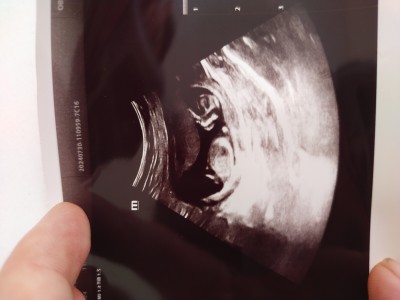

13 haftalık sizce cinsiyeti ne olabilir

İki bacak arasını doktor görse bile söylemez burda çocuğun iki bacak arası bile gözükmüyor keseden felan da cinsiyet söyleyenlere inanma canım daha erken sabırlı ol

Dr ne dedi canım kız gibi benim kızda böyle yayvandı popo kısmı sağlıkla gelsin

Aynı benimki gibi bugün gittim 13 haftalık kıza benziyor dedi . Yine bir ay sonra bakalım dedi değişebilir.